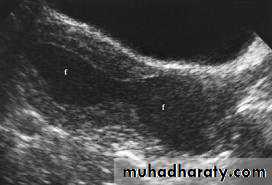

Normal Uterus in longitudinal viewUterine Pathology

• Endometrium

• Post menstruation• Endometrium